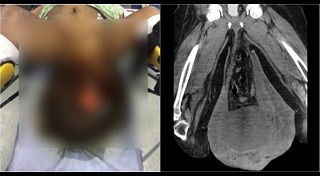

หนุ่มเป็นไส้เลื่อนรุนแรง อัณฑะโต 3 กก. ยานโตงเตงถึงเข่า เป็นแผลเน่าทรมาน

สยองหนักมาก ! เมื่อหนุ่มคนนี้เป็นโรคไส้เลื่อน ไม่ยอมไปรักษา จนกลายเป็นอย่างที่เห็น...

แพทย์ผงะ ! ชายป่วยไส้เลื่อนกว่า 12 ปี อัณฑะใหญ่ยักษ์เท่าลูกฟุตบอล